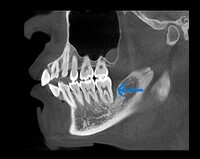

歯科治療の恐ろしさは、少しでも手を抜くと、積み重ねてきた治療効果が全て0=ゼロになってしまうことです。当院では一つ一つの治療過程にベストを尽くすべく、開業当初よりマイクロスコープ、セファロ分析や口腔内スキャンなど最新の機材を取り揃えて、幅広く、深い治療を追求してきました。

私はこれまでの歯科医師人生で、虫歯や歯周病、歯の根にある神経の処置である根管治療、入れ歯、インプラント、美容診療など、幅広く取り組んでまいりました。例えば虫歯治療では、痛みのある歯だけでなく、噛み合わせなどお口の中を総合的に考えたアドバイスや立案をし、歯を長持ちさせる処置を提供することを心がけています。